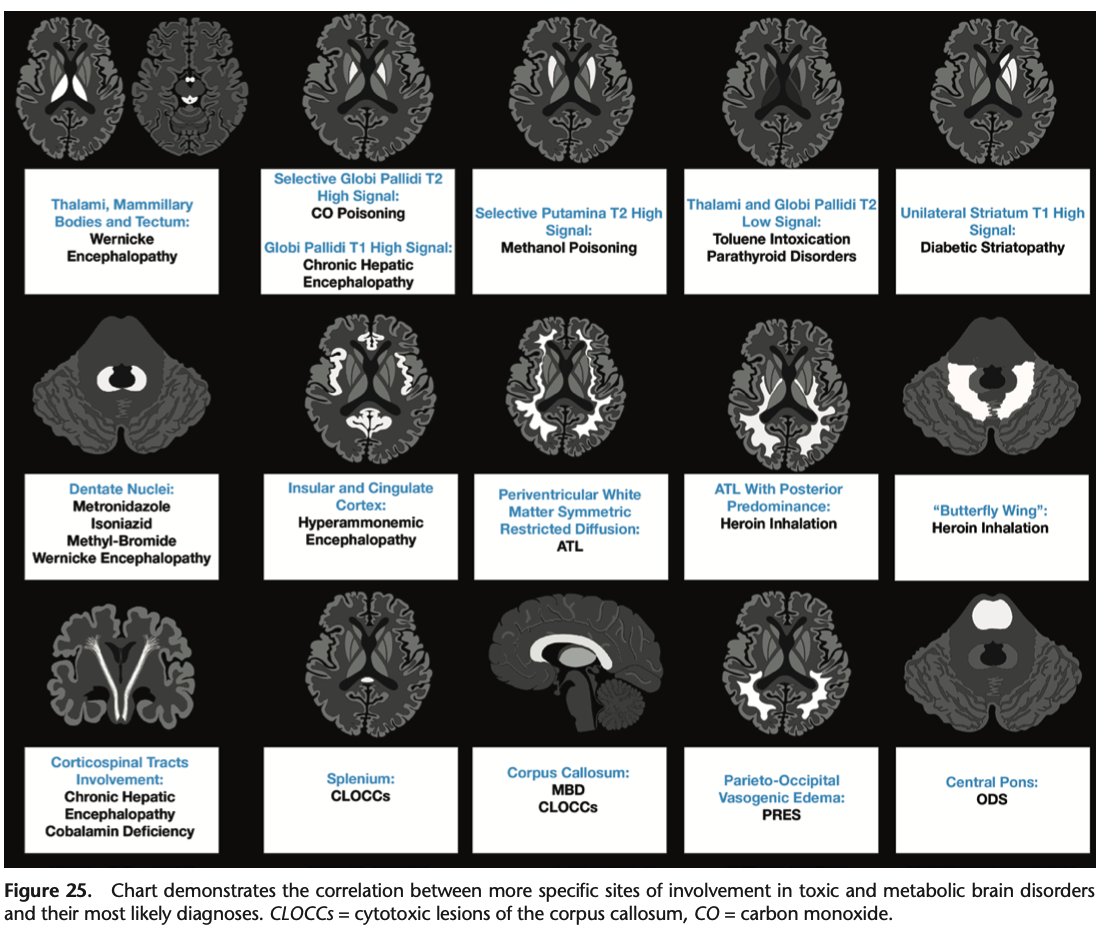

@caseyalbin

Because writing "I dunno.... Looks symmetric. It's probably a metabolic thing" in the chart is generally frowned upon. Love this. https://t.co/dbBRuaSUPG #neurotwitter